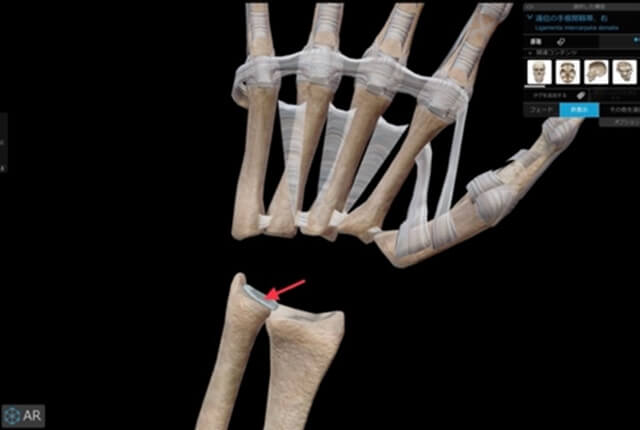

遠位橈尺関節(DRUJ)

橈骨と尺骨の遠位部の関節は遠位橈尺関節(DRUJ)と言います。

DRUJ、尺骨遠位、手根骨をつなぐ支持組織は三角線維軟骨複合体(TFCC)と言います。

三角線維軟骨複合体(TFCC)

尺骨短縮術

plus varianceでDRUJ不安定性がない症例に行います。